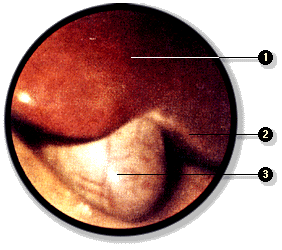

La cavidad peritoneal puede ser explorada directamente mediante la laparoscopía. En este examen se introduce un instrumento óptico, el laparoscopio, y se inyecta gas en la cavidad peritoneal para separa las hojas visceral y parietal del peritoneo. De esta manera es posible recorrer la cavidad e incluso realizar, bajo visión directa, ciertas intervenciones quirúrgicas que no requieren de un abordaje amplio de la cavidad abdominal.